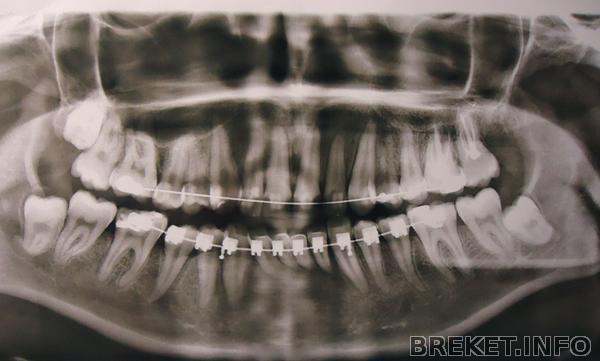

Ребята, удалили мне сегодня вторую по счету 8. Ту которая сверху)

Вырезали с десны, достали. Зашили. Хирург молодой красавчик...ммм..